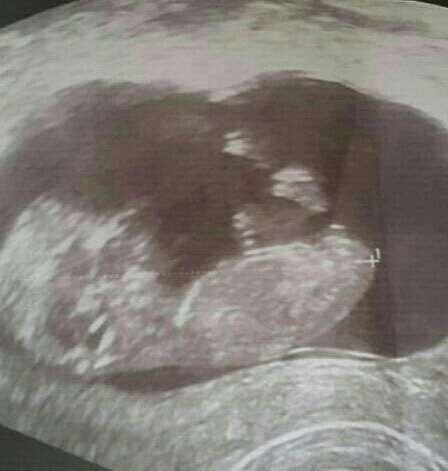

Boy or Girl nub???

Plz tell me

I don't see a nub. Do you have other pictures?